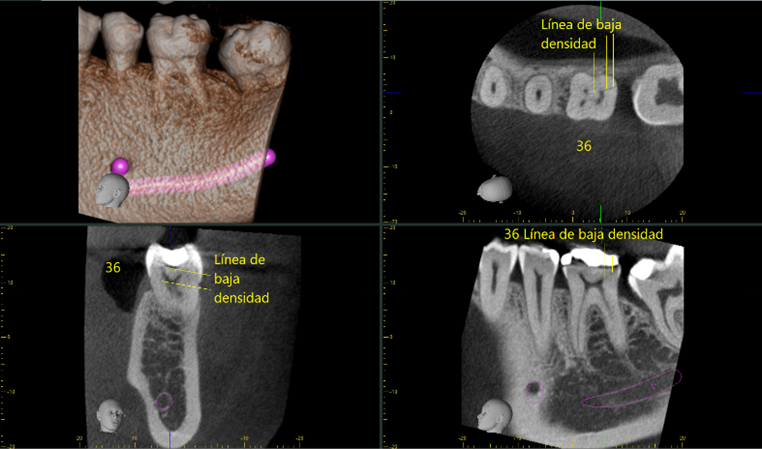

En este caso, se le realiza tomografía al paciente en zona del 36 y al realizar rotación de 360° del diente sobre su propio eje, hay línea de baja densidad en sentido vertical y oblicuo en cara distal y levemente hacia lingual en la corona y tercio cervical radicular, desde la cámara pulpar hacia distal del molar, compatible con fisura por fractura radicular y de la corona, no desplazada en 36. Descartada la posibilidad de estar frente a un artefacto tomográfico. Por eso la evaluación clínica es muy relevante en este caso.